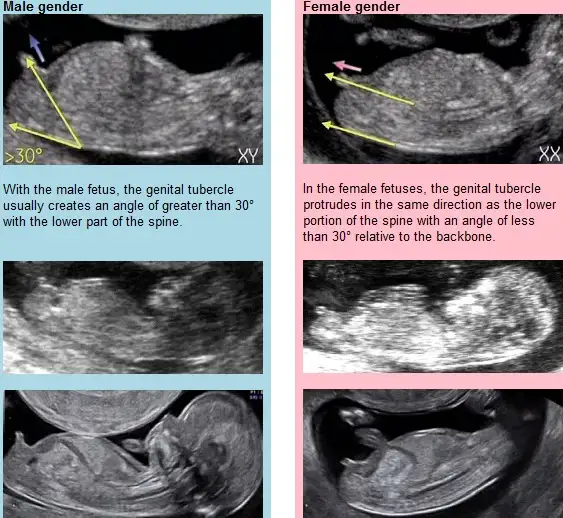

DİK OLURSA ERKEK PARALEL OLURSA KIZ OLUYORMUŞYani? Kusura bakmayın anlamıyorum :)

DİK OLURSA ERKEK PARALEL OLURSA KIZ OLUYORMUŞEki Görüntüle 1413434